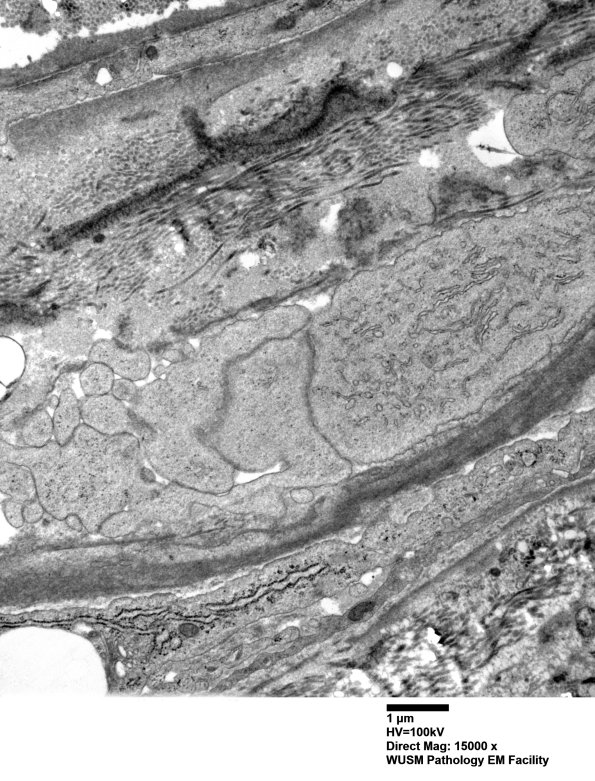

2D5,6 The origin of these processes appears to be from the perineurial cells themselves. (electron micrographs)